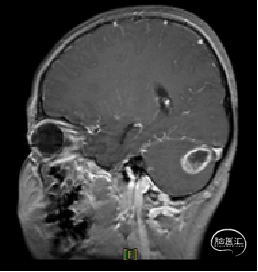

现病史:患者18个月前无明显诱因出现间断头痛,休息后可缓解,开始未予重视,未行特殊治疗。1周前患者无明显诱因出现恶心、呕吐,就诊于当地医院,行颅脑MRI提示:小脑囊实性占位性病变,首先考虑毛细胞星型细胞瘤。现患者为求进一步治疗就诊于我院,门诊以“脑肿瘤”收入院。患者自发病以来神志清,精神可,饮食睡眠正常,二便如常,体重未见明显下降。

术前MRI